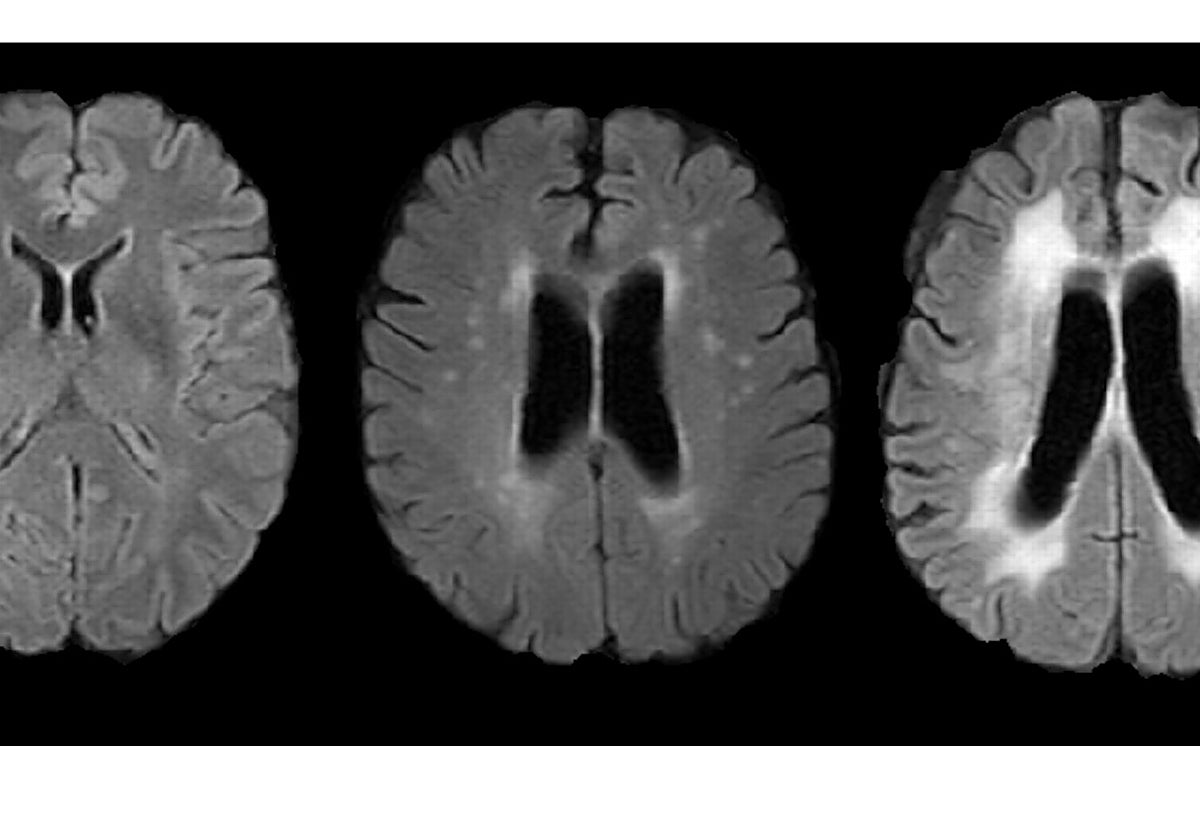

Un estudio del Grupo de investigación Neurovascular del Instituto Hospital del Mar de Investigaciones Médicas, que publica la revista «Biology», ha permitido asociar por primera vez una edad biológica más avanzada con la presencia de un indicador de envejecimiento del cerebro, las hiperintensidades ... de la sustancia blanca, áreas del cerebro donde la sangre llega con más dificultad.

Se trata de áreas del cerebro que aparecen de forma diferente en imágenes de resonancia magnética y que indican que es un tejido donde la sangre llega con más dificultad.

De hecho, la edad biológica explicaría el 42,7% del envejecimiento cerebral medido por la presencia de hiperintensidades de la sustancia blanca. Como detalla Joan Jiménez-Balado, investigador postdoctoral del Grupo de investigación Neurovascular del IMIM-Hospital del Mar y autor del estudio, «hay que seguir estudiando el efecto que tiene la genética sobre estas lesiones del cerebro, ya que puede ayudarnos a entender mejor los mecanismos biológicos que participan en el envejecimiento cerebral. De la misma manera, será muy interesante en futuros estudios utilizar las nuevas aproximaciones informáticas que nos permiten clasificar las hiperintensidades de la sustancia blanca en función de aspectos como su localización y ver si, por ejemplo, sucede que estamos considerando estas lesiones como un todo cuando en realidad se asocian a ellas causas diferentes en función del espacio que ocupan».